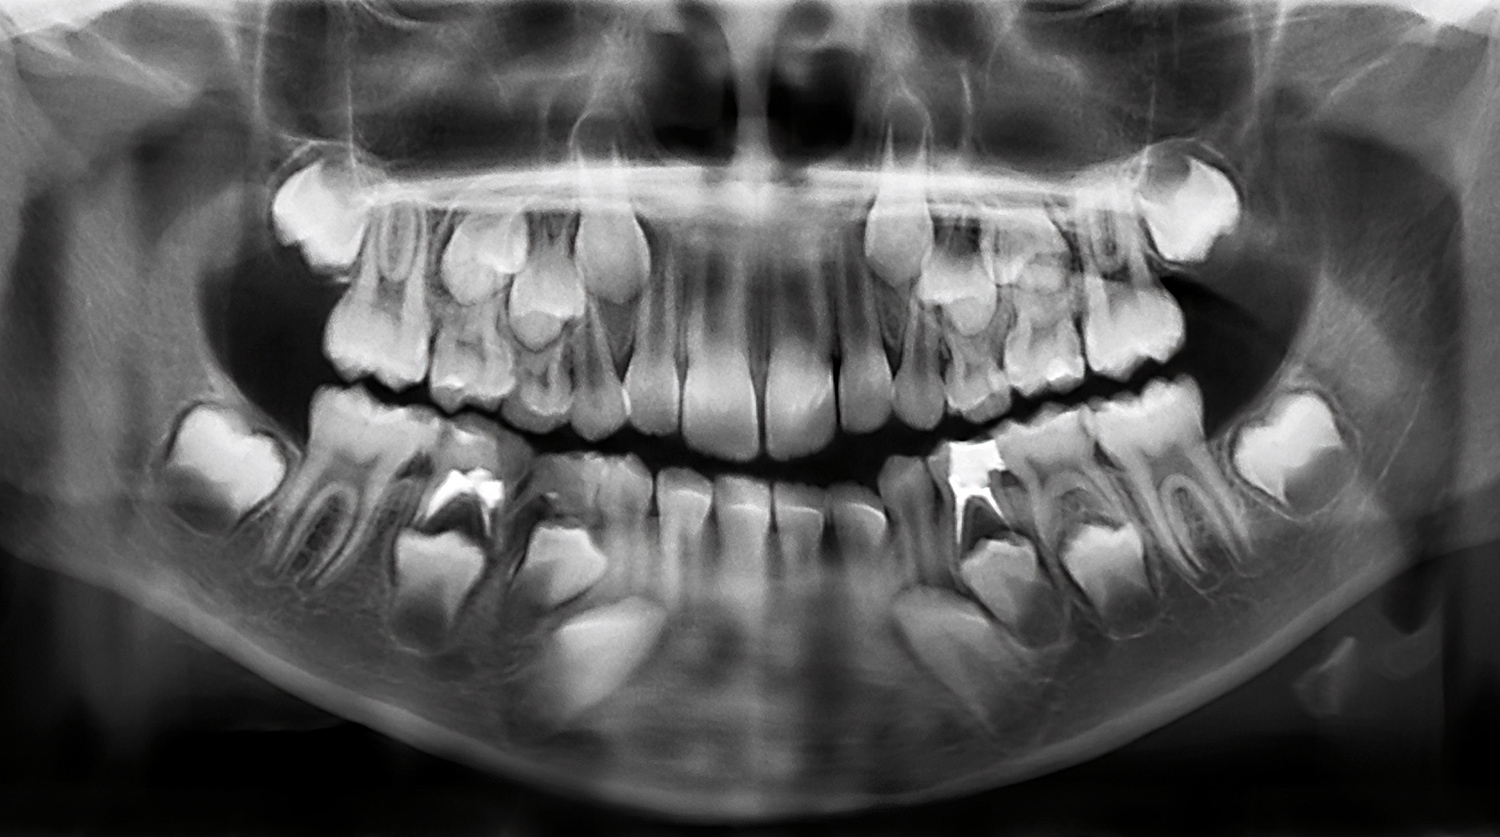

По молочным зубам можно выявить предрасположенность ребенка к психическим заболеваниям, выяснили американские психиатры. Они рассчитывают, что их открытие позволит надежно диагностировать возможные отклонения на ранних этапах.

По молочным зубам можно выявить предрасположенность детей к психическим заболеваниям, обнаружили специалисты из Массачусетской больницы. Исследование было представлено на встрече Американской ассоциации развития науки в Вашингтоне.

Исследователи работали с молочными зубами, выпавшими у шестилетних детей.

Ученые проанализировали зубы 37 детей старше шести лет. Они попросили родителей приносить им выпавшие молочные зубы и затем изучали толщину эмали, объем пульпы и другие показатели. Исследователям удалось установить взаимосвязь между характеристиками зубов и особенностями поведения детей, о которых сообщали родители и учителя.

Зубы начинают формироваться еще на этапе внутриутробного развития и, как поясняют исследователи, хранят информацию о том, что происходило с детьми во время беременности и в первые годы жизни.

«Зубы представляют собой многообещающий новый биомаркер, так как они хранят информацию не только о том или ином нашем жизненном опыте, но и о времени, в которое мы его пережили, — поясняют авторы работы. — Как годовые кольца на дереве связаны с его возрастом, так и изменения в зубах у детей связаны с психическими симптомами».